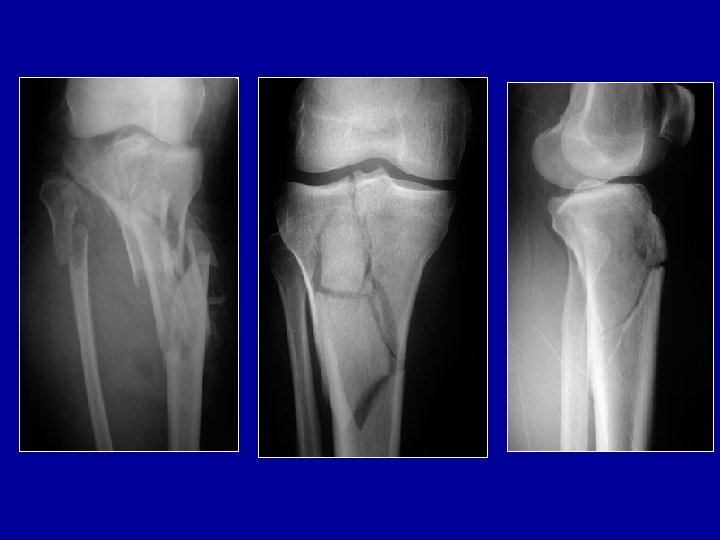

Fractures articulaires

Fractures articulaires Fracture-enfoncement du plateau tibial externe : relèvement + greffe

Fractures articulaires Fracture-séparation du plateau tibial

Fractures articulaires Fracture métaphysaire et des plateaux tibiaux

Fixateur avec combinaison de grosses broches dans le tibia et de fines broches dans la cheville ou le pied Photo J. Chouteau